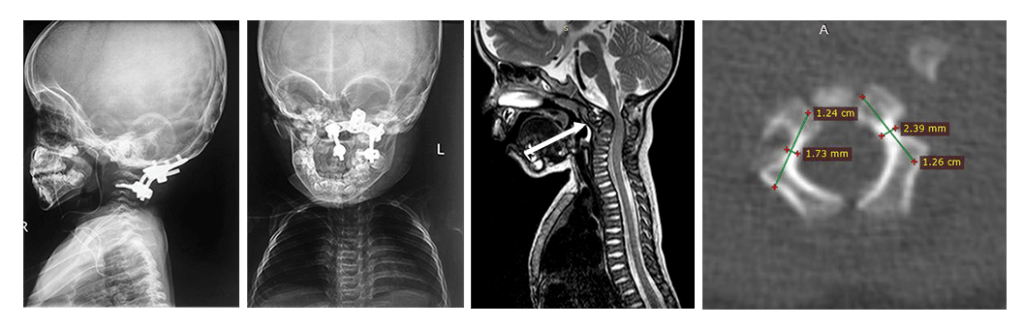

На фото: атланто-аксиальная нестабильность у ребенка 9 лет. Атлант смещен вперед, а спинной мозг оказывается сдавлен между дугой атланта и зубовидным отростком.

На снимках: ребенок 3 лет со спондилоэпиметафизарной дисплазией и тетрапрегией, имеется нестабильность в области краниоцервикального перехода с сдавлением спинного мозга. Стрелкой обозначен смещенный вперед атлант. Очень маленькие размеры позвонков. Проведена фиксация «второй шейный позвонок – затылок», костная пластика. Смещение атланта и нестабильность устранены. Восстановление движений в конечностях после операции. Ребенок самостоятельно начал ходить.

На снимках: пациент 36 лет с атланто-аксиальной нестабильностью и сдавлением спинного мозга на фоне врожденного порока развития «зубовидной кости» (обозначена стрелкой). Тетрапарез после незначительной травмы. Проведена передняя мобилизация для устранения смещения и задняя фиксация с устранением нестабильности, костная пластика.